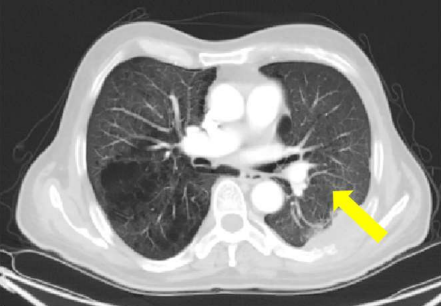

- Did the patient pass away from the lung cancer or from the MUO? He developed cerebral metastasis towards the end of the disease, which is more common in lung cancer compared to MUO. However, MUO generally has a worse prognosis and the CEA was rising. A picture of his X-ray, lung CT and perinephric lesion on CT before death are provided below. You can clearly see that the lung tumour was not locally progressing. It is more likely that he passed away from the MUO. Also, you can see that towards the end of the disease, he developed suspicious subcutaneous soft tissue nodules in the right gluteal region, uncommon to lung cancer .

Fig 10: CT chest before death

Fig 11: CT abdomen